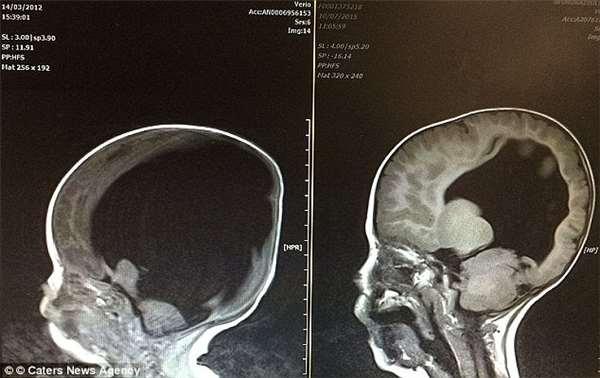

這是因為清走積水前,Noah的大腦組織僅有常人的2%(左圖),不過嚴重的腦積水一引流後,完本空洞的腦組織也開始發育、生長,到3歲那年已長回了八成(右圖)。